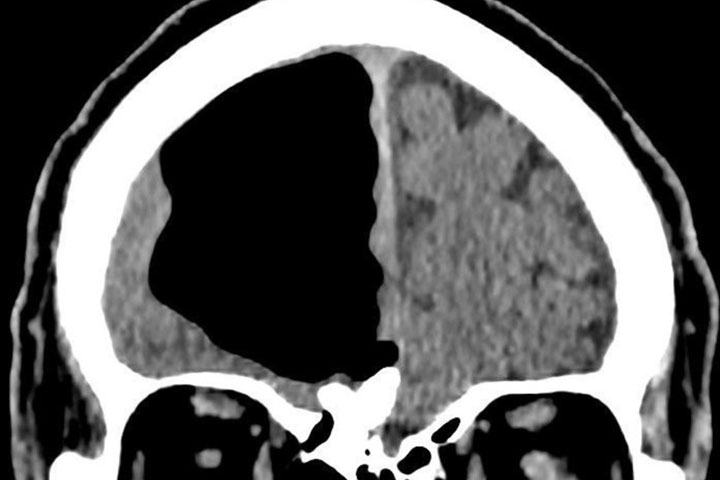

A scan of a man from Northern Ireland, showing a major cavity in his skull. BMJ Case Reports 2018

A CT scan revealed a nine-centimetre air-filled cavity in his right frontal lobe, looking like a big black blank area on the scan.